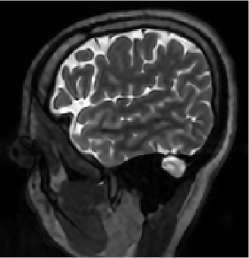

The MRI data used for this study were acquired using a 3D T2 CUBE sequence with Cartesian readouts using a -channel head coil. The matrix dimensions were 256 232 208 with mm isotropic resolution. Fully sampled multi-channel brain images of five volunteers were collected out of which data from four subjects were used for training, while the data from the fifth subject were used for testing. Since the readout is fully sampled, we evaluated the inverse Fourier transform of each readout. We retrospectively undersampled the phase encodes to train and test the framework; we note that this approach is completely consistent with a future prospective acquisition, where a subset of phase encodes can be pre-selected and acquired. All the experiments were performed with variable-density Cartesian random sampling mask with different undersampling factors mentioned at their use.

Figures 7 and 8 visually compare two different slices at 4x and 8x accelerated data acquisition in the presence of Gaussian noise of . The testing slices are from a subject, whose data was not used for training. It is evident from the zoomed portions that the reconstruction quality by the proposed method is better than the techniques compared against.